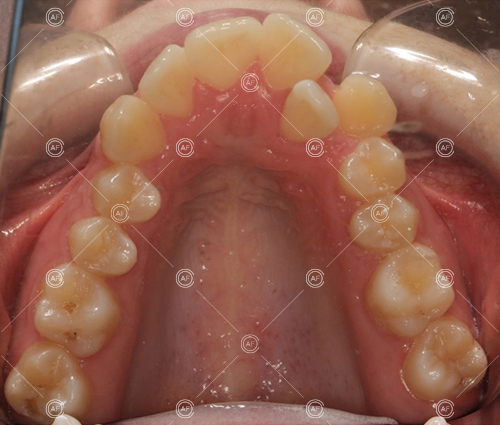

The aim of the treatment was to relieve upper and lower arch crowding, correct lower centre line shift, treat class 1 incisors and buccal segments.

MH debonded in December 2020, with overall treatment time of around 14 months.

She was provided with upper and lower vacuum form retainers, and asked to wear these every night for the first year, and alternate nights for the second year onwards, indefinitely for as long as she wanted her teeth to remain straight. High quality finish was maintained at one year post-debond.